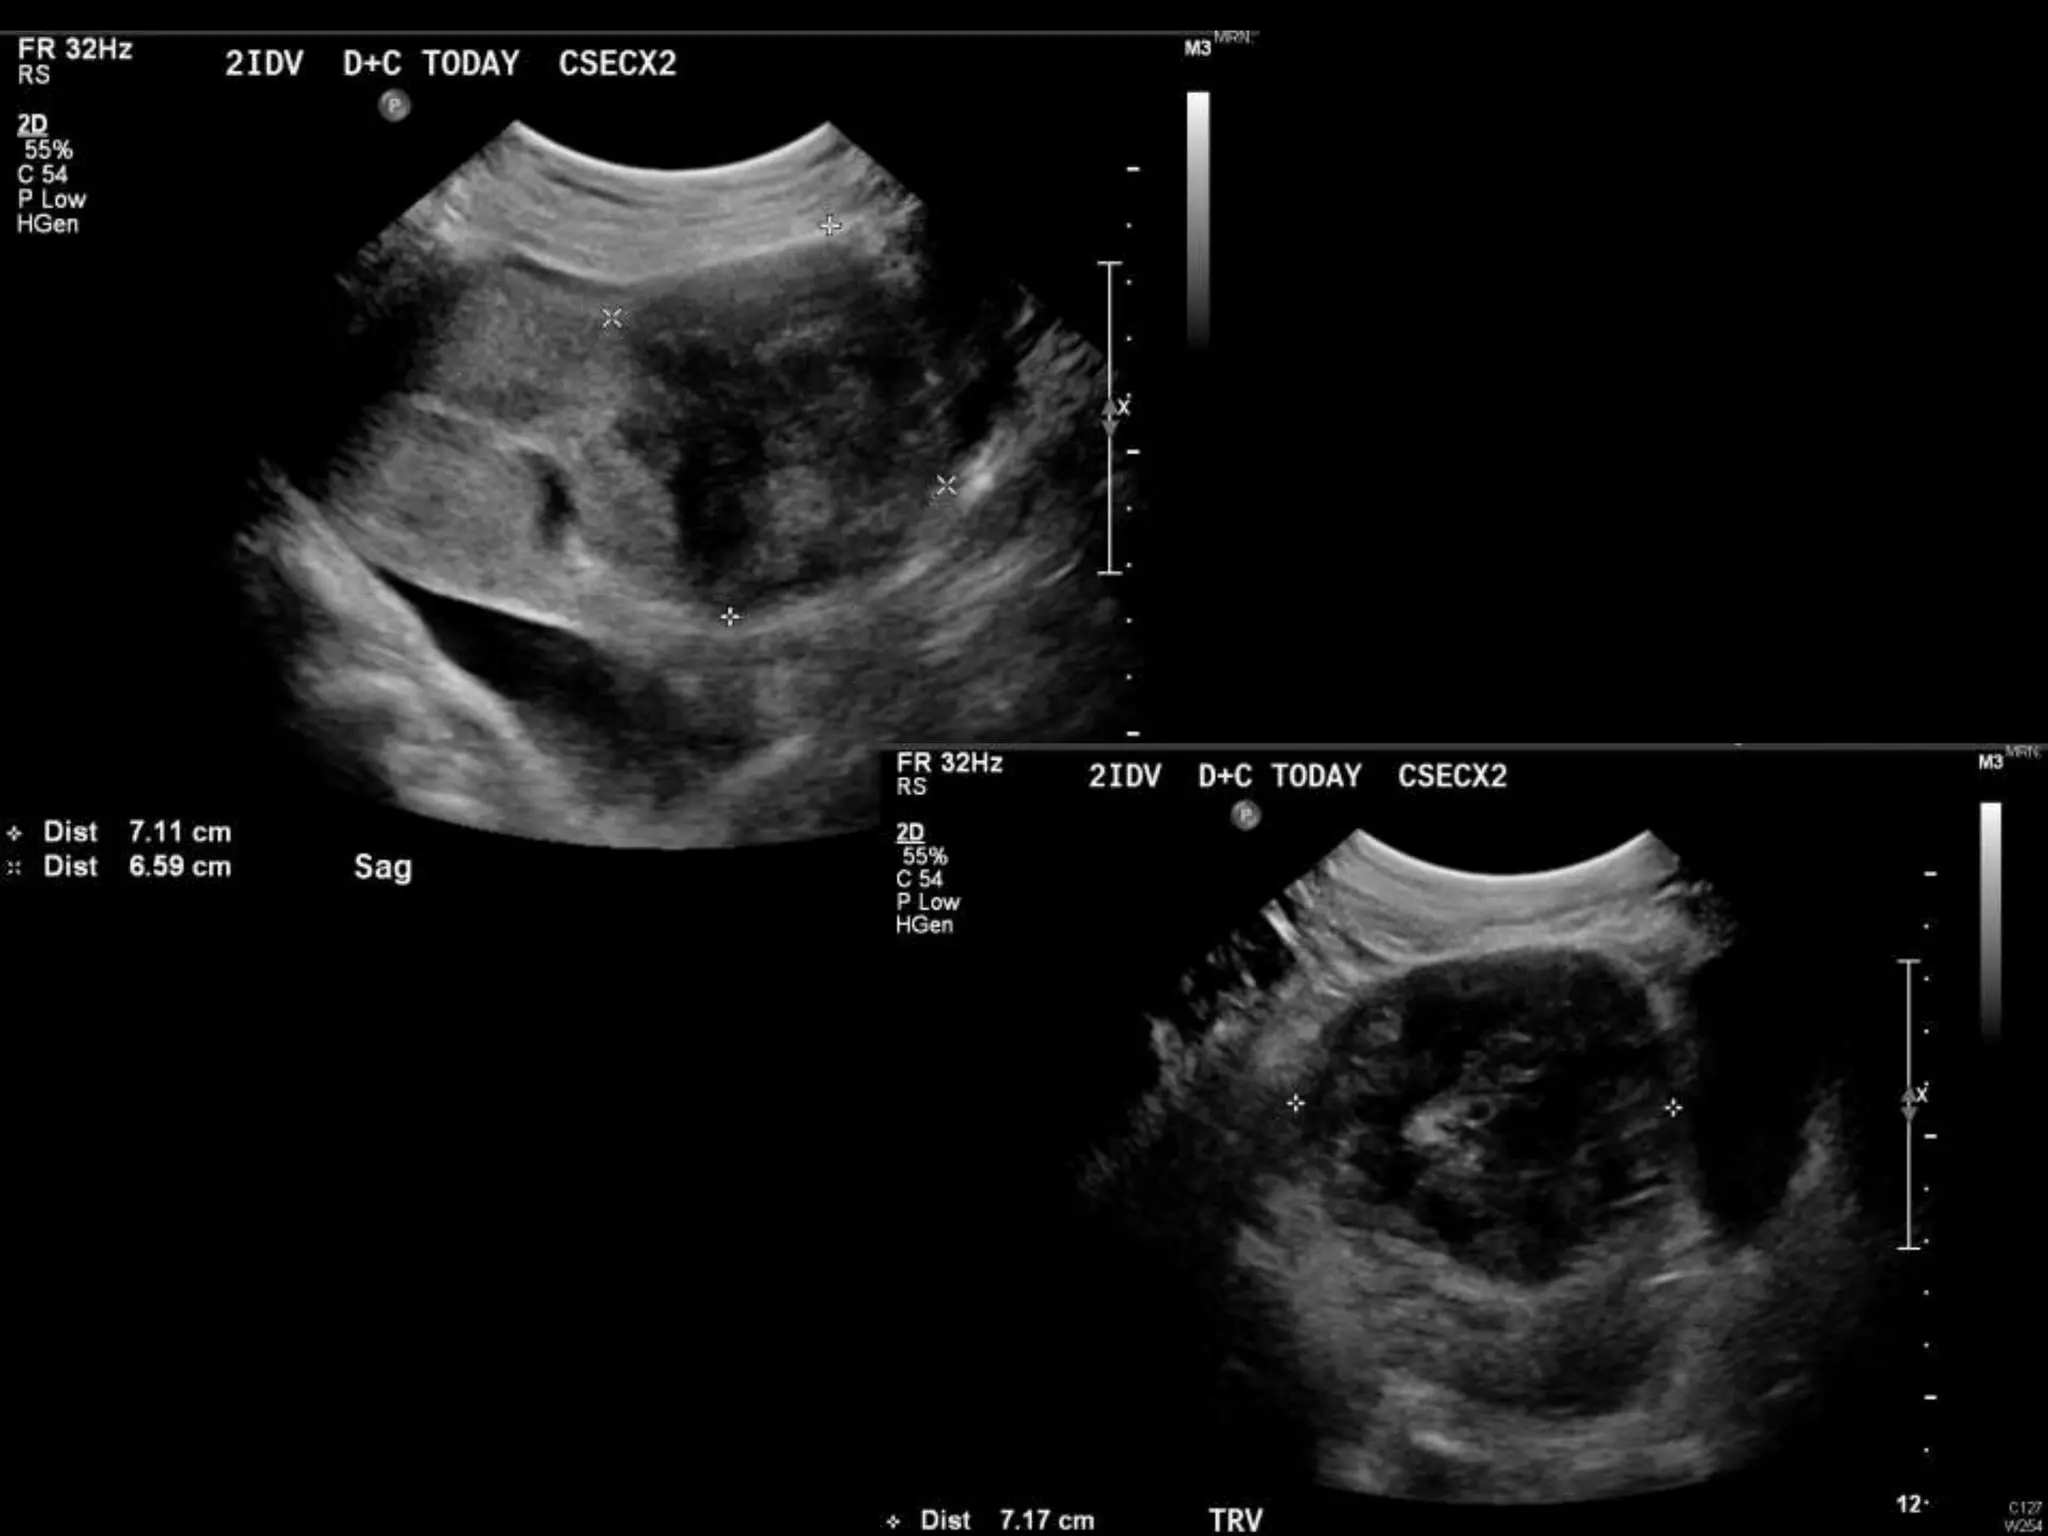

Dr. Anne Silas

HISTORY

โ€ข 40 yo female 8.5 weeks pregant

โ€ข S/P D&C for pregnancy implanted at site of

c-section scar

โ€ข 6 weeks post D&C patient presents with

heavy persistent bleeding

โ€ข For Pelvic US

โ€ข HCG = 451 mIU/mL

D&C complicated byPerforation, AVM w RPOC at Site of Perforation โ€ข AVM โ€“ Acquired or Congenital โ€ข Acquired โ€“ Traumatic โ€“ D&C, TAB, uterine surgery โ€“ Less common: Endometrial / Cervical CA, GTD โ€“ Clue on US: numerous tortuous vessels, high velocities โ€ข Tx: โ€“ transcatheter arterial embolization โ€ข Potential to preserve fertility โ€“ UA ligation, hysterectomy

POST PROCEDURE S/P embolizationof right UA and left UA due to cross collateralization

1 month followup HCG < 5 mIU/mL No flow in area โ€“ smaller in size Felt residual hematoma Will continue US follow up